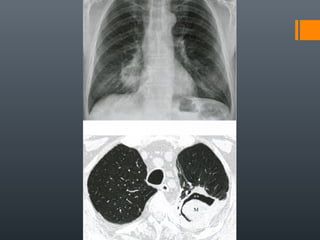

O documento discute vários conceitos radiológicos incluindo consolidação, atelectasia, nódulos, pseudocavidades e padrões intersticiais, fornecendo definições, sinais e diagnósticos diferenciais para cada tópico. Ele também discute a redução da atenuação pulmonar e fornece um link para mais informações.